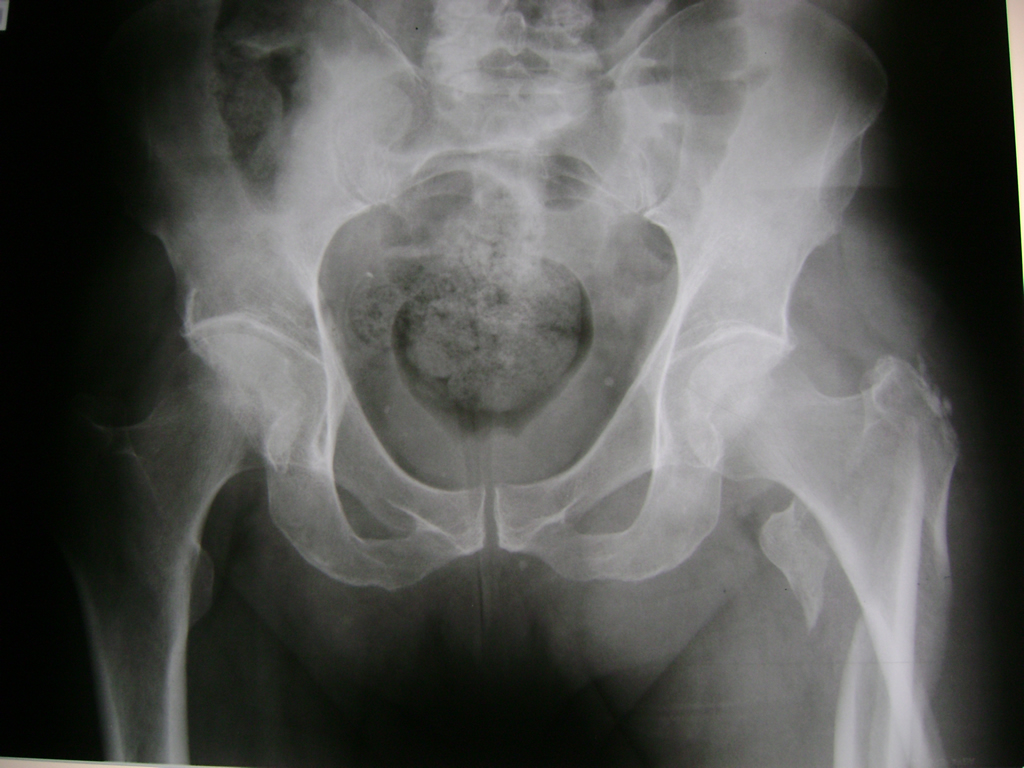

La cirugía de fractura de cadera se realiza para reparar una ruptura en la parte superior del hueso del muslo. Este hueso se denomina fémur.

Es parte de la articulación coxofemoral. Si una fractura de cadera no recibe tratamiento, es posible que deba permanecer en una silla o en la cama.

Esto puede llevar a otros problemas de salud potencialmente mortales, sobre todo si usted es una persona mayor.